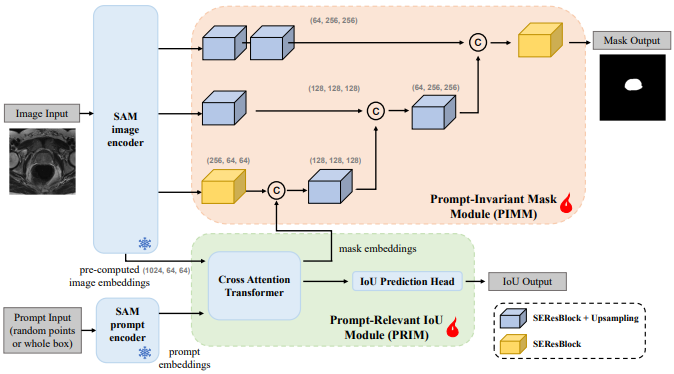

DeSAM

DeSAM:提出了将 SAM 的掩码解码器分成两个子任务:提示相关的 IoU 回归和提示不变的掩码学习。DeSAM 最小化了错误提示在“分割一切”模式下对SAM性能的降低。